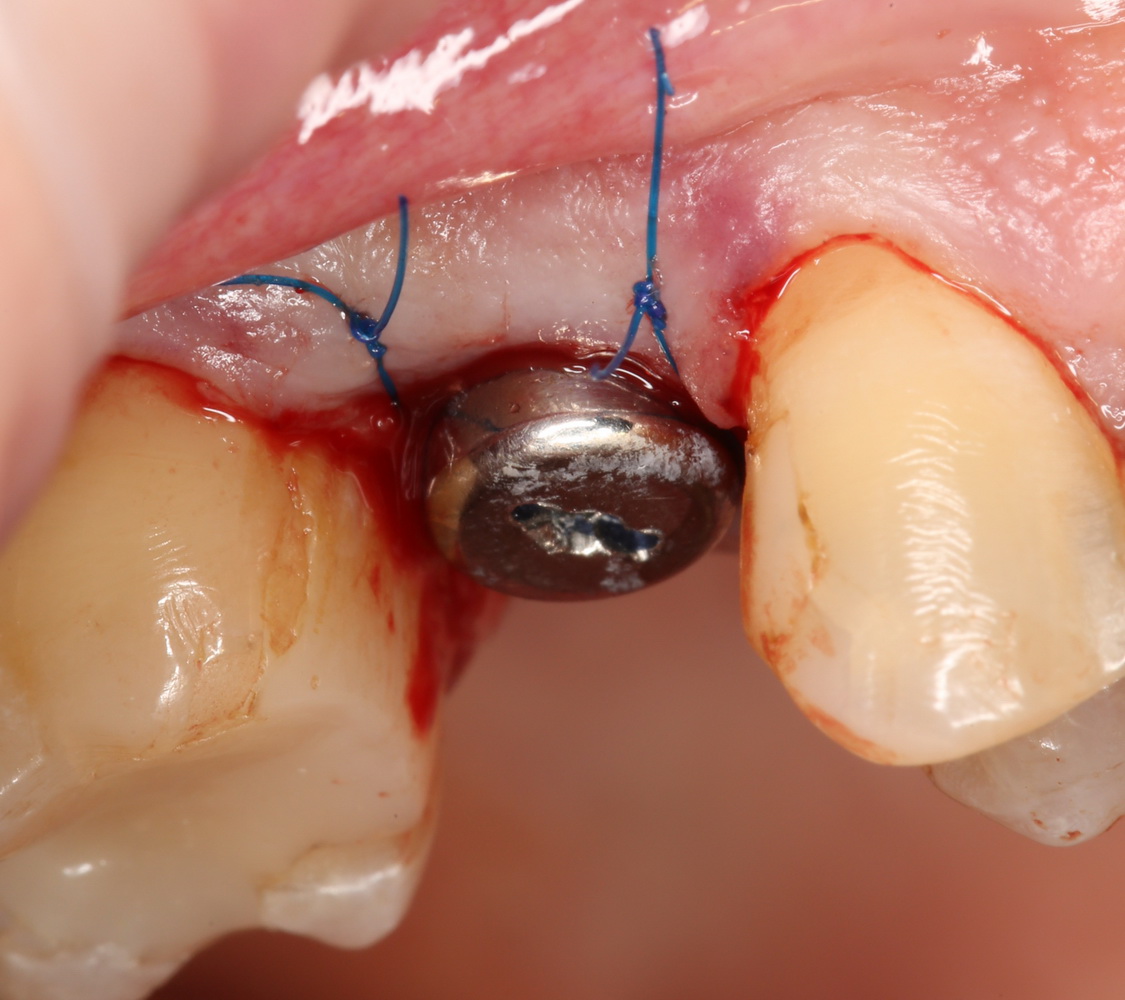

Что мы и сделали. Удалили зуб:

Критически важно провести удаление аккуратно, чтобы не разрушить и без того тонкие стенки альвеолы. Вообще, в хронометраже операции немедленной имплантации удаление зуба занимает 75% времени, это наиболее сложная и деликатная часть вмешательства.